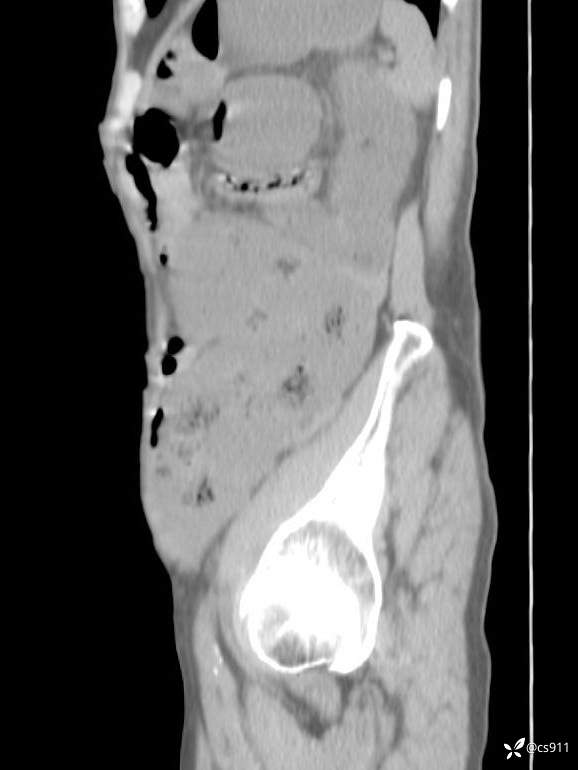

急腹症之急诊CT,原因?答案公布

男,77岁,腹痛、腹胀伴恶心呕吐1天。呕吐胃内容物,非喷射性呕吐,有咖啡色样胃内容物,诉有胃穿孔病史。查体:全腹平,下腹部压痛,全腹无反跳痛,叩诊呈浊音,移动性浊音阴性,肠鸣音减弱,1-2次/分。肛检:直肠未扪及明显肿物,可触及大量粪块。

T 36.6℃ P 80次/分 R 26次/分 BP 100/60mmHg

白细胞(WBC) H 14.55 10e9/L 4-10

红细胞(RBC) 4.58 10e12/L 4.3-5.8

中性粒细胞百分率(NEUT%) H 85.7 % 40-75

血淀粉酶(AMY) HH 1859 U/L 35-135

癌胚抗原(CEA) H 27.44 ng/ml 0-5

呕吐物 潜血试验 * 阳性 阴性

患者轮椅入室检查神志清楚, 能配合摆位和呼吸